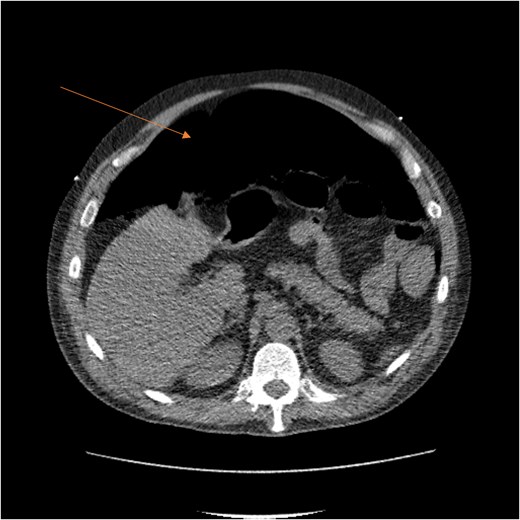

Laboratory results showed thrombocytopenia and erythrocytosis, with a hemoglobin level of 18.6 g/dl and platelets at 840 00/μl. A CT scan of the abdomen and pelvis was ordered to rule out malignancy or paraneoplastic syndrome causing the VTE (Fig. 1). The CT showed no lesions suspicious for malignancy but revealed a left RSH, managed conservatively.